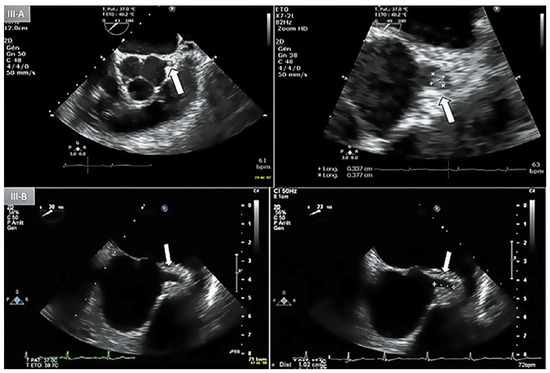

Myocardial Infarction due to Obstruction of the Left Main Coronary

Case report